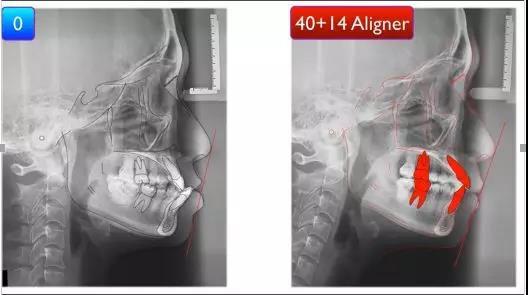

前后全景片的对比显示,一开始后牙是近中倾斜的,通过治疗,矫治后后牙直立,牙根平行度改善明显。

通过侧位片的分析,下颌都内收明显,可以看到面型得到改善。

我们再把侧位片进行术前术后的重叠分析,可以看到下颌是往下旋转,所以原来较短的脸型稍微被拉长了,

上颌的后牙做了远倾的效果,上前牙进行了唇展的同时也稍稍伸长了一点,使前牙更加美观。

下颌后牙是进行了远移和直立,前牙进行了压低,避免内收的同时后期前牙造成早接触。